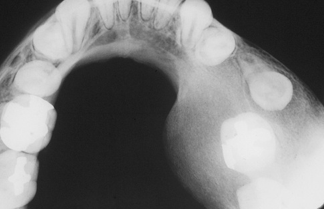

florid cemento-osseous dysplasia